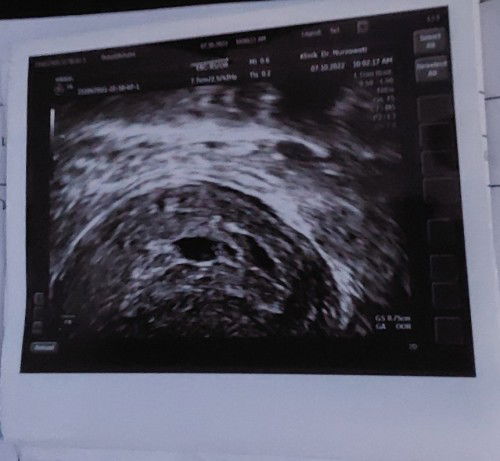

Baru balik klinik sebab ada bleeding sikit.. doctor scan hari tu ckp kantung size dah 0.63cm.. lepas 2 minggu scan balik...doctor klinik suggest buka buku pink ..dan time buka buku scan kat KK dia org ckp size kecil lagi kantung tu..tapi no heartbeat ..Hari nie ada bleeding sikit.. pergi scan doctor ckp kantung size 0.75cm, tapi kantung nampak tak cantik.. and baby ada tissue je dalam kantung..tak dapat detect heartbeat semua..scan Dari bawah..sebab Rahim terbalik.. Saya rasa risau stress.. ada siapa siapa mcm nie..Saya Punya 2 anak pun nampak bila dah 2 bulan lebih....#ingintahu #pleasehelp